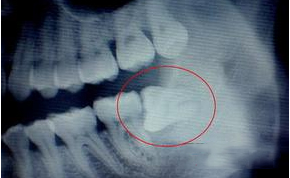

二 智齿引起的牙龈肿痛

智齿是指人类口腔内牙槽骨上最里面的第三颗磨牙,从正中的门牙往里数刚好是第八颗牙齿。 智齿处持续疼痛,碰触牙龈疼痛加剧,严重的伴随嘴张不开,经常发炎症者,建议炎症消除后尽快拔除智齿。有的顾客的位置长的不正确,会引起蛀牙,也是建议拔除的。